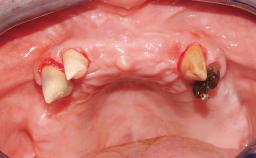

A 31-year-old man presented to our clinic 30 days after a motor vehicle accident in which he had suffered a dentoalveolar fracture in the anterior maxilla, including avulsion of teeth 12 and 11 and luxation of tooth 21. He was first treated on the night of the accident in a small city hospital with no oral and maxillofacial surgeon on the staff. A wired retention had been applied and the teeth repositioned to the best of the clinicians’ abilities. When he first presented to our care, the patient showed extrusion of teeth 12 and 11 associated with gingival recession due to bone loss in the anterior maxilla, and the stainless steel wires were still present.

Bone Volume Horizontally and vertically sufficient Horizontally deficient Deficient vertically or deficient vertically AND horizontally

Bone Volume Deficient vertically or deficient vertically AND horizontally